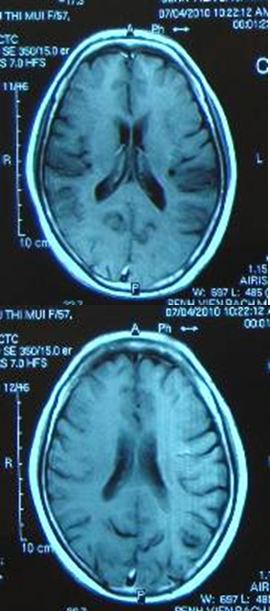

Trường hợp thứ 2: Bệnh nhân Vũ Thị M. , nữ 56 tuổi được phát hiện khối u máu thể hang vùng đỉnh trái kích thước 19mm. Bệnh nhân được điều trị xạ phẫu bằng dao gamma quay liều 20Gy. Sau điều trị 3 tháng tổn thương u máu đã tan hết

Trước điều trị: Khối tổn thương u máu thể hang

tại thùy đỉnh trái kích thước 19mm, hình màu đen

bên trong hình đỏ.

Sau xạ phẫu dao gamma

quay 3 tháng: Khối u máu đã tan hết